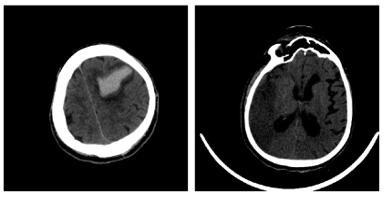

Figure 6 depicts the image samples from the dataset for Hemorrhagic and Ischemic Brain Stroke. In Figure 6, the left side image represents the Hemorrhagic stroke brain image and right-side image represents the Ischemic Brain Stroke. Figure 7 depicts the results after thresholding process and Figure 8 depicts the results after normalization. Performance metrics like recall, precision, f1-score, loss and accuracy are considered to evaluate the proposed model. The performance obtained by the proposed model for 10 trials is presented in Table 3.

Figure 6. Input images from dataset